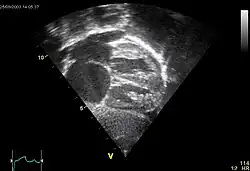

Echocardiography

In transthoracic echocardiography, an atrial septal defect may be seen on color flow imaging as a jet of blood from the left atrium to the right atrium.

If agitated saline is injected into a peripheral vein during echocardiography, small air bubbles can be seen on echocardiographic imaging. Bubbles traveling across an ASD may be seen either at rest or during a cough. (Bubbles only flow from right atrium to left atrium if the right atrial pressure is greater than left atrial). Because better visualization of the atria is achieved with transesophageal echocardiography, this test may be performed in individuals with a suspected ASD which is not visualized on transthoracic imaging. Newer techniques to visualize these defects involve intracardiac imaging with special catheters typically placed in the venous system and advanced to the level of the heart. This type of imaging is becoming more common and involves only mild sedation for the patient typically.

If the individual has adequate echocardiographic windows, use of the echocardiogram to measure the cardiac output of the left ventricle and the right ventricle independently is possible. In this way, the shunt fraction can be estimated using echocardiography.

- 1 2 3 "UOTW #54 – Ultrasound of the Week". Ultrasound of the Week. 30 July 2015. Retrieved 27 May 2017.